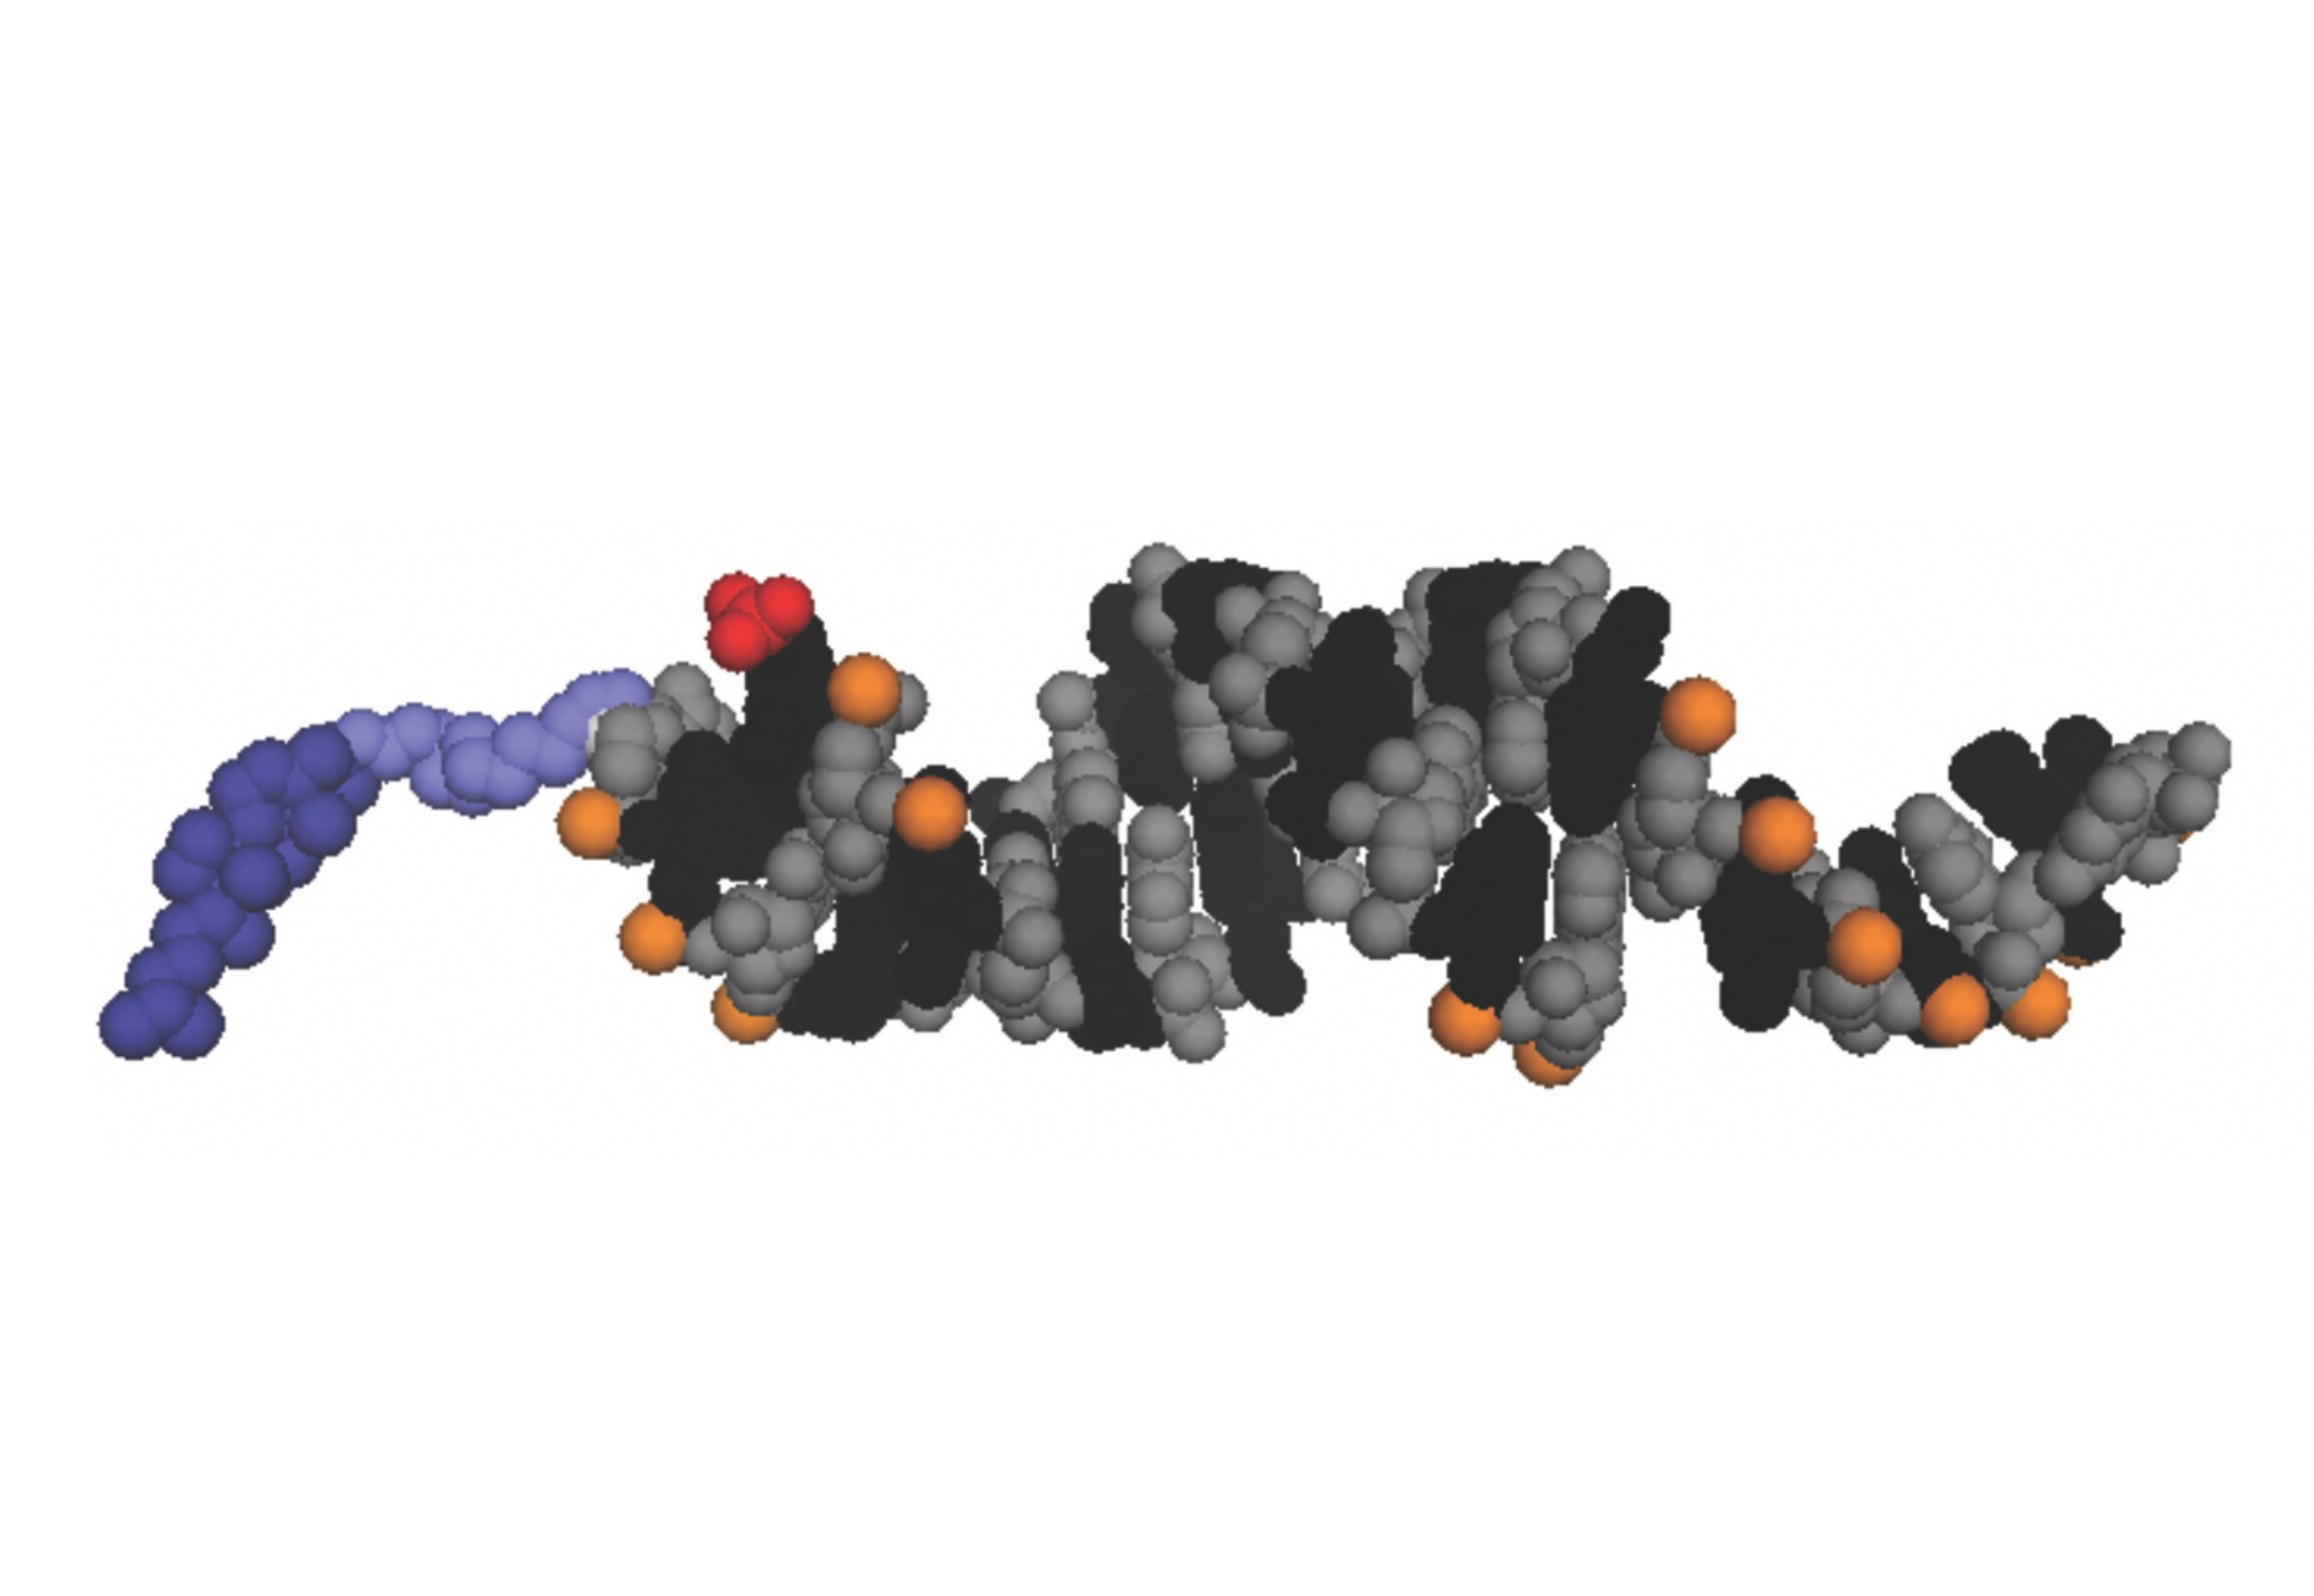

MAY 2, 2017, New publication from the Khvorova & Aronin labs. Synthesis and Evaluation of Parenchymal Retention and Efficacy of a Metabolically Stable, O-phosphocholine-N-docosahexaenoyl-L-serine siRNA Conjugate in Mouse Brain. Nikan M, Osborn MF, Coles AH, Biscans A, Godinho B, Haraszti R, Sapp E, Echeverria D, DiFiglia M, Aronin N, and Khvorova A. Just Accepted Manuscript. Bioconjugate Chem, doi: 10.1021/acs.bioconjchem.7b00226

MAY 2, 2017, New publication from the Khvorova & Aronin labs. Synthesis and Evaluation of Parenchymal Retention and Efficacy of a Metabolically Stable, O-phosphocholine-N-docosahexaenoyl-L-serine siRNA Conjugate in Mouse Brain. Nikan M, Osborn MF, Coles AH, Biscans A, Godinho B, Haraszti R, Sapp E, Echeverria D, DiFiglia M, Aronin N, and Khvorova A. Just Accepted Manuscript. Bioconjugate Chem, doi: 10.1021/acs.bioconjchem.7b00226